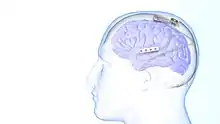

The use of neurostimulation to treat epileptic seizures is only recommended in those who have failed multiple medications for the treatment of their seizures. The NeuroPace RNS system was approved for use by the FDA in 2013 and is the only medical device for epilepsy that uses responsive neurostimulation.[1] The device is surgically implanted into the patient's head with electrical leads placed near the site in the brain that is believed to be the origin of the patient's seizures. These leads record electrical activity in the brain and deliver electrical stimulation when a seizure is detected.[9] The device keeps a record of abnormal electrical activity that is reviewed by a neurologist to improve the detection and treatment of seizures. The patient is able to record when they are having symptoms with the device to see if their symptoms are correlating with seizures.[1] The use of responsive stimulation has found to be effective for seizure reduction. Some patient's are able to achieve complete seizure freedom with responsive and non-responsive neurostimulation.[10]